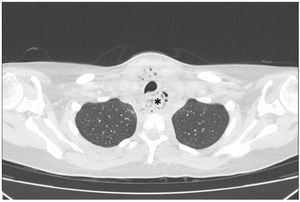

Paciente mujer de 17 años con antecedentes de meningoencefalitis en la infancia sin secuelas, que consultó por un cuadro clínico de una semana de evolución consistente en dolor cervical, odinofagia y fiebre de hasta 39°C. En la exploración física las constantes fueron estables, presentando dolor cervical a la movilización. En la analítica presentó elevación de reactantes de fase aguda. Se realizó una TAC cervical y torácica en la que se observó una gran colección cervical con abundantes burbujas de gas en su interior (figs. 1-3, asteriscos), con extensión hacia el mediastino posterior a través del espacio peligroso retrofaríngeo, hallazgos compatibles con fascitis necrosante y mediastinitis posterior. En las muestras quirúrgicas se cultivó Streptococcus dysgalactiae y S. intermedius. La paciente evolucionó favorablemente con tratamiento antibiótico y drenaje quirúrgico de la colección.